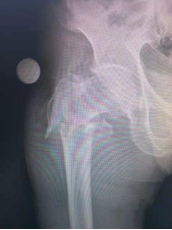

1.股骨粗隆间骨折—PFNA内固定术(微创)